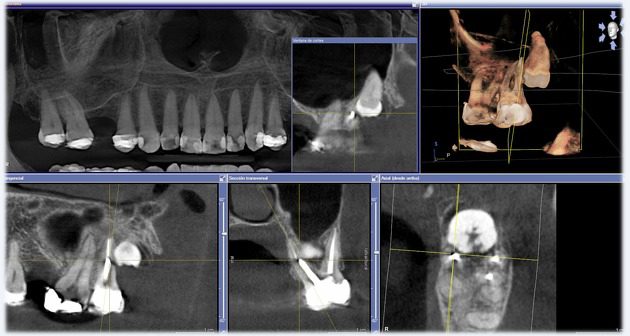

Description de l'examen

Le Cone Beam est un examen d’imagerie 3D en haute résolution qui permet d’obtenir une visualisation très précise des dents, des mâchoires, des sinus et des structures osseuses. Cet examen est couramment utilisé en implantologie, en chirurgie dentaire ou pour rechercher une lésion difficile à voir en radiographie classique.